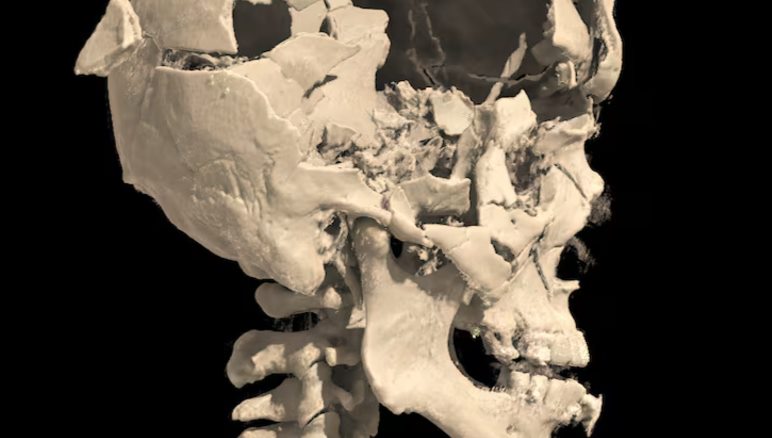

Imagens divulgadas pela Polícia Federal nesta segunda-feira (18) mostram que parte do crânio de Francisco Wanderley Luiz, autor do atentado em frente ao STF (Supremo Tribunal Federal), ficou destruído após ele ter explodido uma bomba perto da própria cabeça.

Segundo exame de tomografia, o lado direito da cabeça dele foi parcialmente destruído, e também houve rachaduras em outras áreas do crânio.

“Constatou uma fratura extensa, com abertura do crânio no lado direito, e várias fraturas com amputação dos dedos na mão direita. O que é compatível, nos permite inferir, que essas regiões estavam próximas no momento da explosão, ou seja, provavelmente, ele segurou a bomba com a mão direita próximo da própria cabeça”, disse o boletim do médico legista.